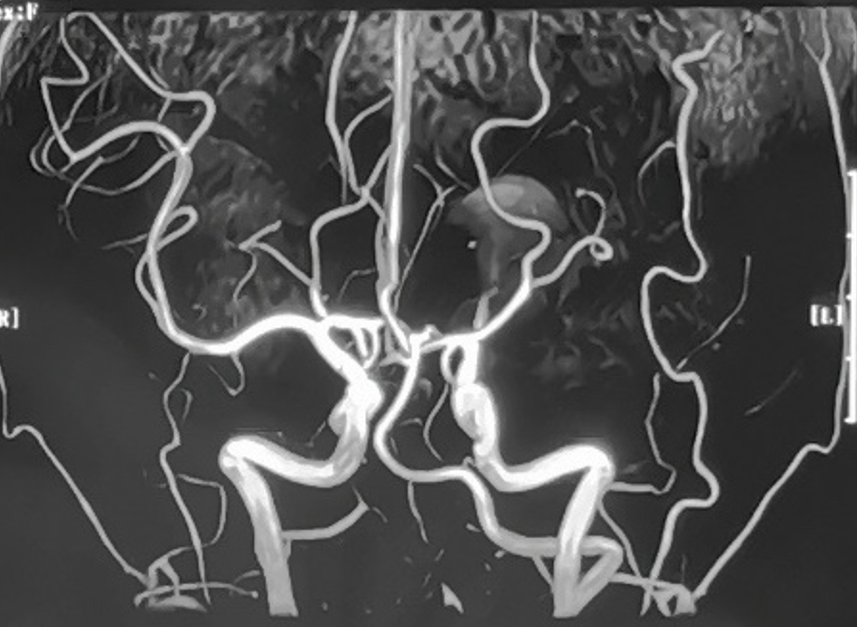

性别:女性,年龄:33 y.o

影像学阳性

术前诊断:

术中电生理未见明显异常,因此未进行进一步血流重建处理。